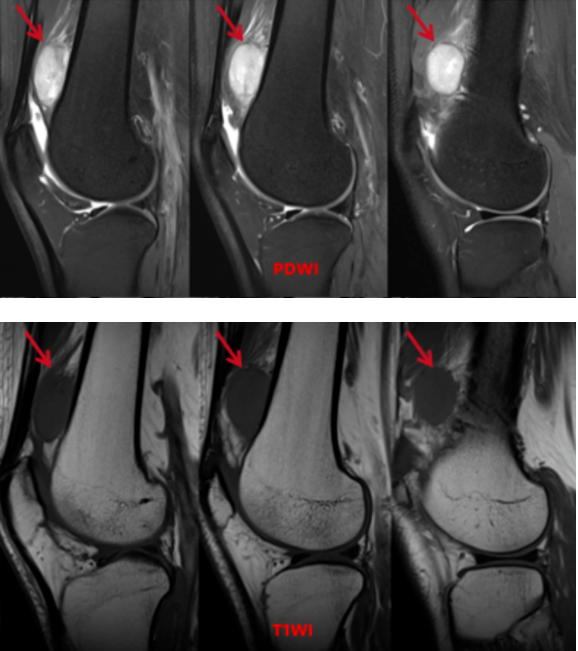

左膝关节MRI平扫:左股骨下段骨干前方软组织内(股中间肌与股外侧肌交界区)可见类圆形团块状稍长T1信号,PDWI呈稍混杂高信号,大小约15x32x37mm,边界清晰,其内信号欠均匀、可见点线状低信号,病灶边缘欠规整,邻近周围软组织见少许条片絮状片高信号,相应骨质未见破坏。

影像诊断:左股骨下段骨干前方占位,倾向于良性可能性大,筋膜来源肿瘤性病变-结节性筋膜炎可能,建议临床活检

鉴别诊断:滑膜血管瘤、腱鞘巨细胞瘤、恶性纤维组织细胞瘤

多参数、多序列成像:MRI可以利用不同的扫描序列(如T1WI、T2WI、PDWI、脂肪抑制序列等),从多个“角度”反映组织的不同物理和生化特性。这有助于判断病变的 成分(如是否含水多、含脂肪、含纤维、含血)、边界、与周围重要结构(如血管、神经)的关系,从而为鉴别肿瘤的良恶性、推断其来源提供丰富信息。